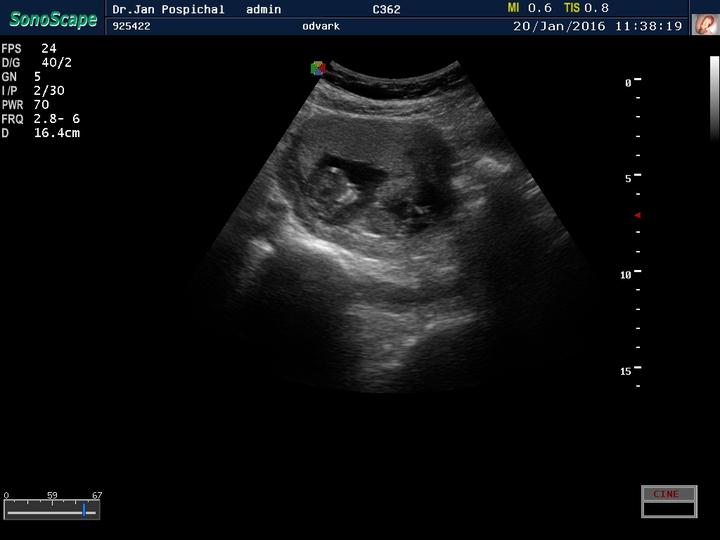

Zdravím Vás dámy 🙂 tak dnes kontrola 20+1tt a už nám potvrdili že budeme 100% chlapák 🙂 fotečku bohužel nemám, mám video ale to netušim jak se sem dává 🙂 vše je v pořádku a rosteme jako z vody... délka od hlavičky k zadečku 15cm a váha 400g... už ted se těšim až náš poklad zase uvidim 🙂